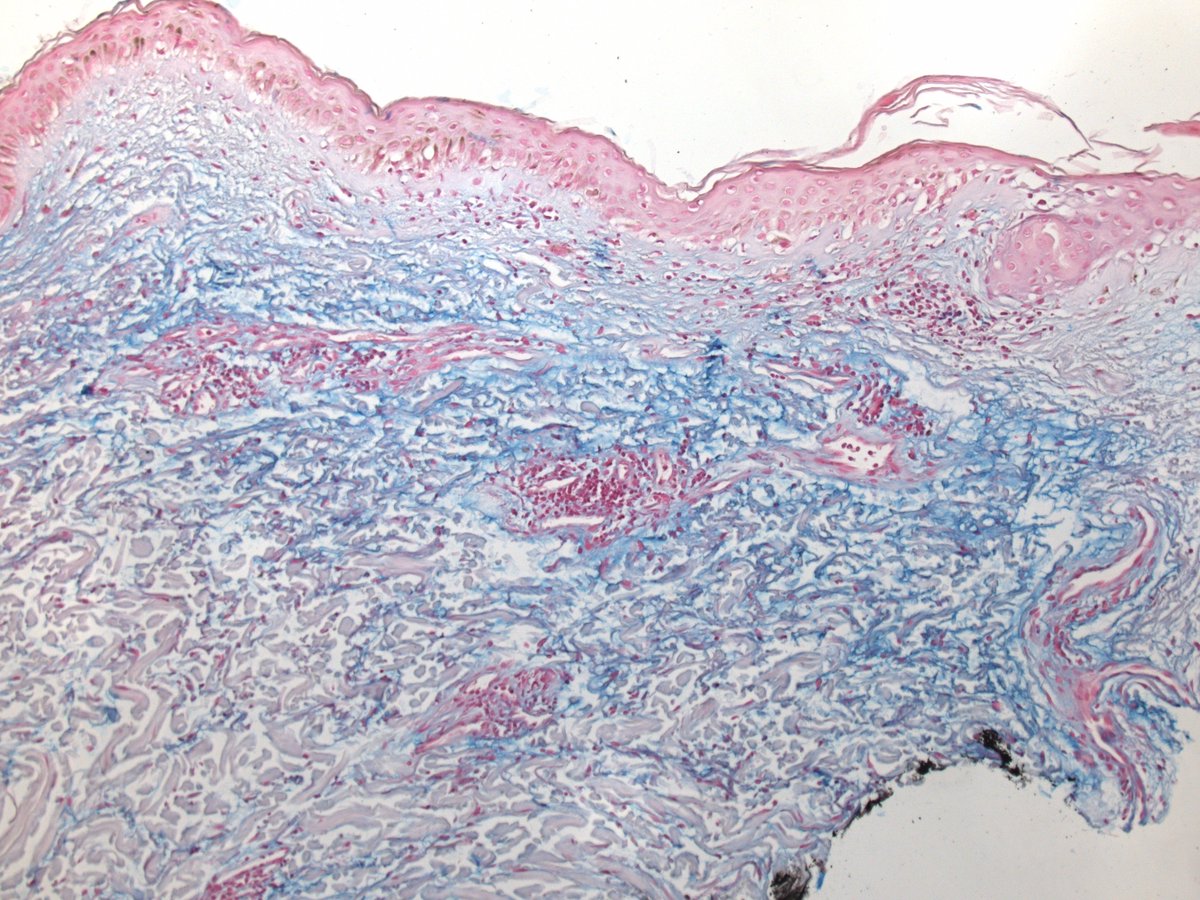

Histological findings in dermatomyositis are rather non-specific. Interface changes and dermal mucin seem most consistent. #dermpath #pathology